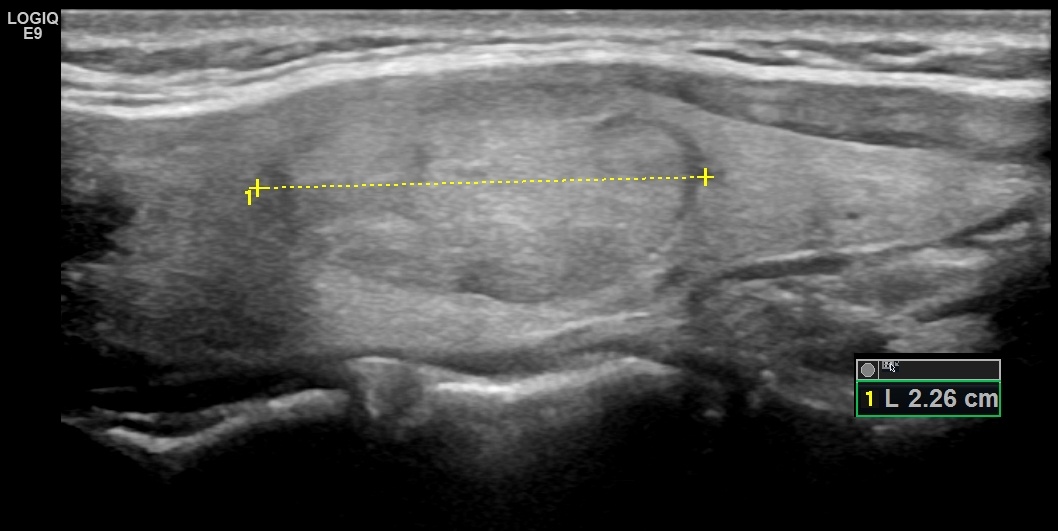

Размеры узлов. Как правило, при определении линейных показателей, никаких особых сложностей не возникает, за исключением случаев выявления узлов с очень нечетк

Как правило, при определении линейных показателей, никаких особых сложностей не возникает, за исключением случаев выявления узлов с очень нечеткими контурами или выражено неправильной формы, при которой контрольные точки измерений могут выбираться врачами УЗД в разных местах, из-за чего размеры могут различаться. Но, как правило, разброс размеров при измерении одного и того же очага различными специалистами незначителен. Следует учитывать, что узлы в щитовидной железе нередко окружены гипоэхогенным ободком "хало", который, при измерении размеров, обязательно должен быть включен в измерение, поскольку является частью узла.